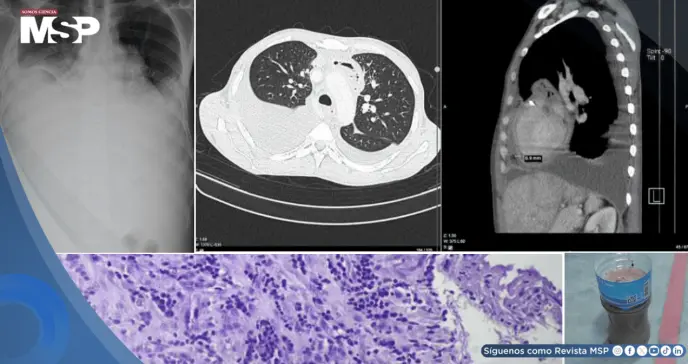

Inicialmente, sus síntomas hicieron pensar a los médicos en una neumonía combinada con una insuficiencia cardíaca. Las radiografías confirmaron la presencia de una gran cantidad de líquido en ambos pulmones.

Los médicos descubrieron que el problema no solo estaba en sus pulmones, sino también en el corazón: un ecocardiograma reveló que este órgano estaba siendo comprimido por una acumulación de líquido en el pericardio, la membrana que lo recubre. Esta condición, conocida como taponamiento cardíaco, es una emergencia.

De inmediato, se realizó una pericardiocentesis, un procedimiento para drenar el líquido que oprimía al corazón. Para sorpresa de los médicos, se extrajeron 950 mililitros de pus, lo que confirmó que el paciente sufría de una pericarditis purulenta, una infección grave en el saco pericárdico.

Frasco lleno de pus extraído tras la pericardiocentesis.

A pesar de que los análisis específicos del pus (como cultivos y la prueba GeneXpert) no lograron identificar la bacteria responsable, el nivel extremadamente bajo de glucosa en el líquido era un indicio claro de infección.

Esta condición, llamada pericarditis constrictiva, requería una intervención quirúrgica definitiva: una pericardiectomía. Durante la cirugía, los cirujanos encontraron exactamente eso: un pericardio fibrótico y grueso que envolvía el corazón, el cual fue extirpado.

Según los autores (Proches, V. et al) el análisis final del tejido pericárdico mostró una inflamación crónica consistente con una infección, pero, una vez más, no se visualizaron los bacilos de la tuberculosis bajo el microscopio.